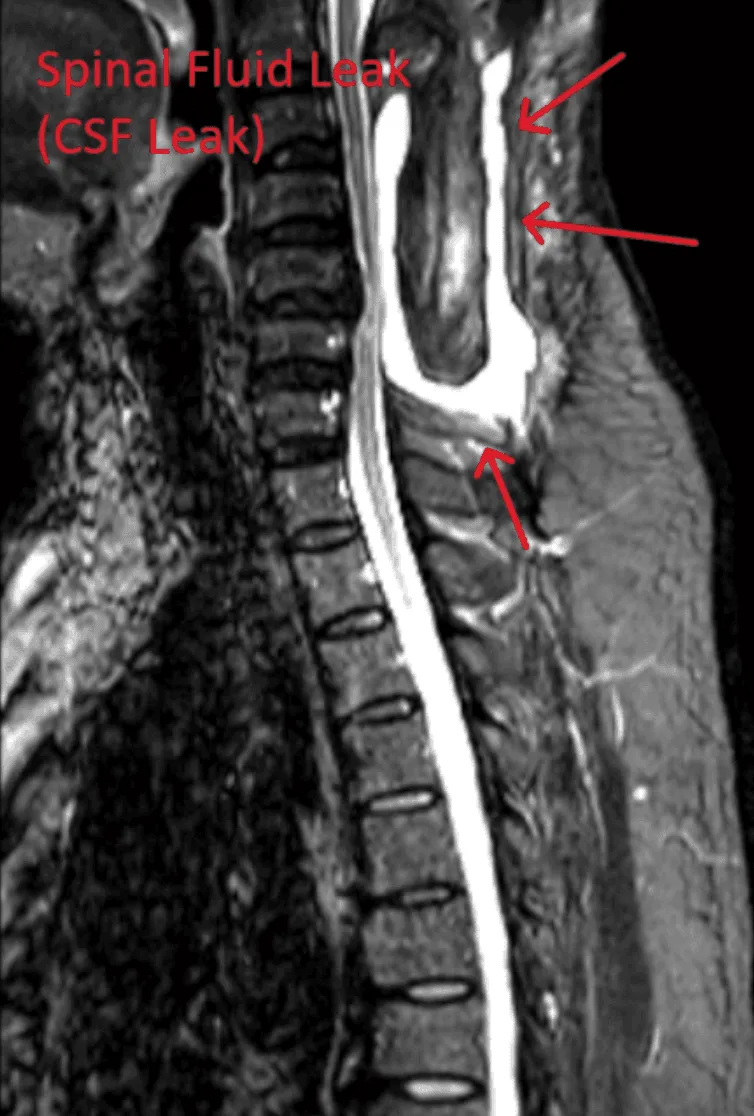

MRI showing a spinal fluid leak with red arrows indicating the affected area.

Spinal Fluid Leak

Dural tears during lead placement leading to cerebrospinal fluid leaks, requiring additional repair surgery.